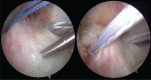

Arthroscopic techniques are considered the gold standard for treatment of displaced avulsion fractures of the anterior cruciate ligament. However, most arthroscopic surgical techniques and fixation methods are technically demanding and require removal of hard implant. This report describes a new, easy, safe, and all-arthroscopic method for reduction and fixation of displaced tibial intercondylar eminence fractures by using 1 anchor and 1 Pushlock.From January 2015 to June 2017, 8 adult patients with type II and III displaced tibial intercondylar eminence fractures were operated using this technique. Clinical assessment included patient demographics, cause of injury, delay before surgery, operation time, time to return to work and sport, International Knee Documentation Committee scores, and Lysholm knee scores.The average operation time was 48 minutes. The average follow-up period was 12.5 months. At the 6-month follow-up, all patients had acquired fracture union and complete functional recovery and were able to return to work. International Knee Documentation Committee objective scores and Lysholm knee scores were 92.4 (range 88-94) and 93.6 (range 90-96), respectively. At the last follow-up, anterior drawer, Lachman's test, and pivot shift tests were negative, and all patients had returned to their preinjury activity levels.Arthroscopic fixation by use of 1 anchor and 1 Pushlock is an easy, safe, and minimally invasive technique for treatment of displaced tibial intercondylar eminence fractures and does not require further surgery to remove fixation devices.Level of Evidence: Level IV, therapeutic case series.